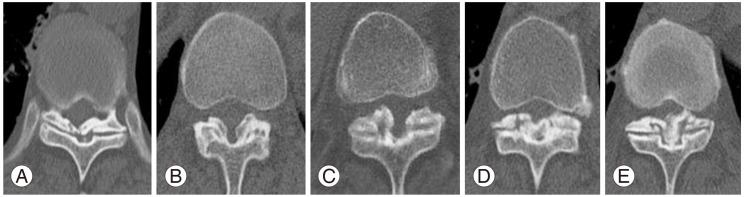

Ossification of the ligamentum flavum is a rare cause of thoracic myelopathy. It develops in East Asians more frequently than in people from other areas. The exact pathophysiology has not been elucidated yet; however, it largely depends on biomechanical alterations, especially changes in the tensile force. Because the spinal cord is compressed from the posterior side, the first and most common clinical manifestation is usually loss of functional gait and spastic paralysis, which develop as the spinal cord compression progresses. The choice of diagnostic imaging is T2 sagittal magnetic resonance imaging scanning. Whole spine scanning is mandatory to identify multiple areas of compression and any associated distal lumbar diseases. Fine computed tomography imaging is necessary to make a differential diagnosis and set up a precise surgical plan. Conservative treatment does not work in this disorder. Decompression surgery is the only option and prognosis after surgical treatment is better with this disorder than with other causes of thoracic myelopathy. The severity of preoperative symptoms and the time interval before surgical treatment are the most important prognostic factors.

黄韧带骨化是胸段脊髓病的罕见病因。东亚地区的发病率高于其他地区。确切的病理生理学尚未阐明;然而,其很大程度上取决于生物力学改变,尤其是张力变化。由于脊髓从后侧受到压迫,最初且最常见的临床表现通常是功能性步态丧失和痉挛性瘫痪,随着脊髓压迫的进展而出现。诊断性影像学检查选择T2矢状面磁共振成像扫描。必须进行全脊柱扫描以识别多个压迫部位以及任何相关的远端腰椎疾病。精细的计算机断层扫描成像对于进行鉴别诊断和制定精确的手术方案是必要的。保守治疗对这种疾病无效。减压手术是唯一的选择,并且与其他胸段脊髓病病因相比,这种疾病手术治疗后的预后更好。术前症状的严重程度和手术治疗前的时间间隔是最重要的预后因素。